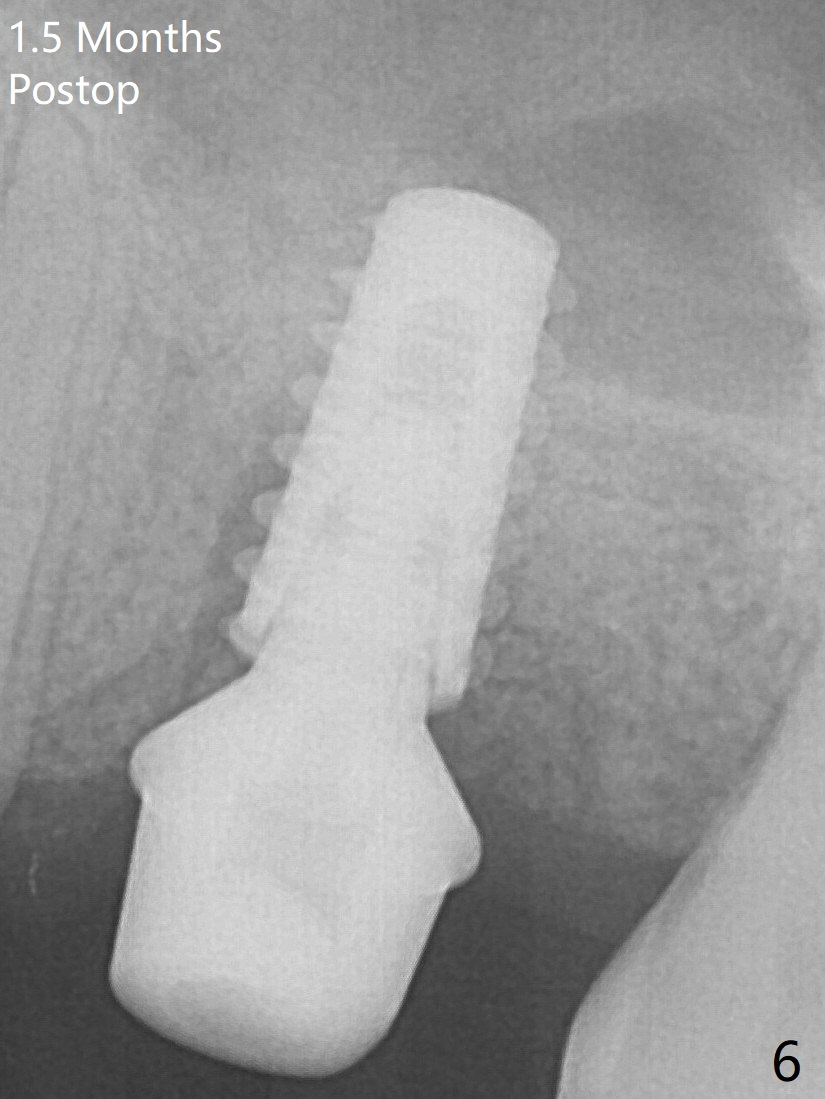

A 5x9 mm implant is placed slightly mesial; after placement of a 6.5x4(2) mm abutment and insertion of collagen plug in the palatal socket (radiolucent area distal to the implant), Vera graft is placed in the remaining socket space (Fig.5 *).  Nasal hemorrhage persists 1.5 months postop (Fig.6).   The distal gingiva is slightly tender and erythematous; a 6x4 mm healing abutment is placed 2.5 months postop (Fig.8).